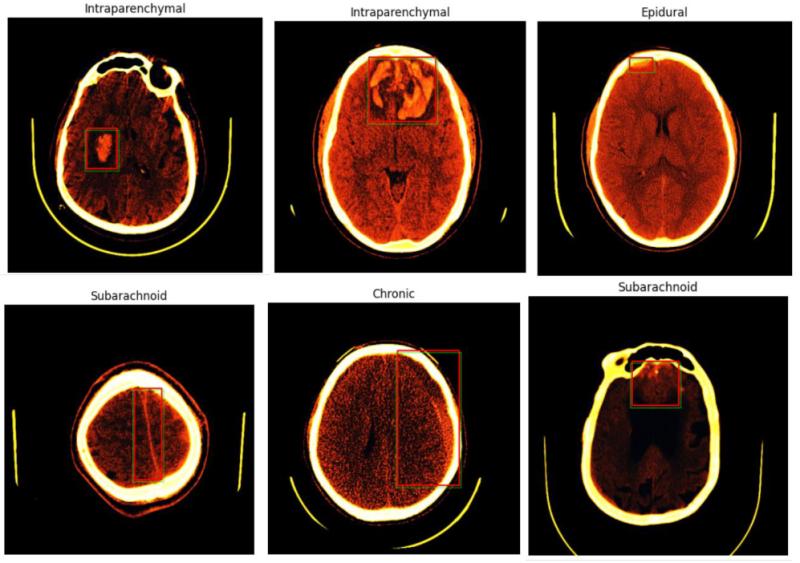

Developed a brain hemorrhage detection and localization system to identify intracranial hemorrhages. Three models were analyzed, with their performance metrics evaluated, leading to the selection of ResNet150 for its superior effectiveness in identifying intracranial hemorrhages. Six windowing methods were implemented, and after thorough analysis, the sigmoid BSB method was determined to be the most effective. The system involved preprocessing data from a CSV file, matching it with the SOP Instance UID, and subsequently opening the corresponding DICOM images and labels for further analysis. This project was a collaborative effort between Rushrn Dianayake and me, where we contributed to model selection, performance evaluation, and data preprocessing to enhance the system’s accuracy and efficiency.

Results image 1

Results